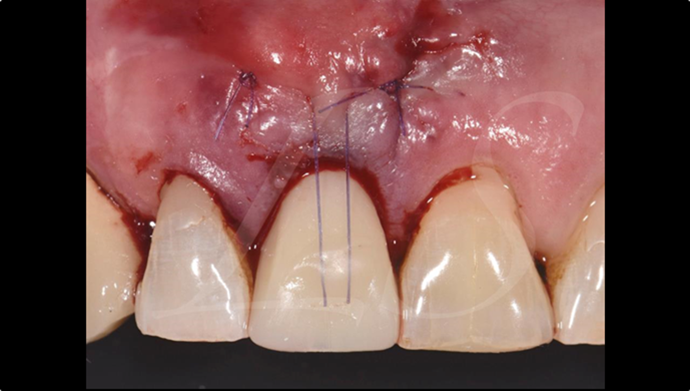

Clinical case: : R2GATE guided surgery & immediate implant placement

- Courtesy of Dr. Kwang Bum Park, Korea -

Dr. Kwang Bum Park, immediate loading, digital guided surgery, digital ONE-DAY implant, maxillary anterior, #21, guided surgery, immediate loading, AnyRidge, R2GATE, Mega ISQ, MEG Torq, R2GATE Full Surgical Kit

implant system, R2GATE Guide, R2GATE full surgical kit, Mega ISQ